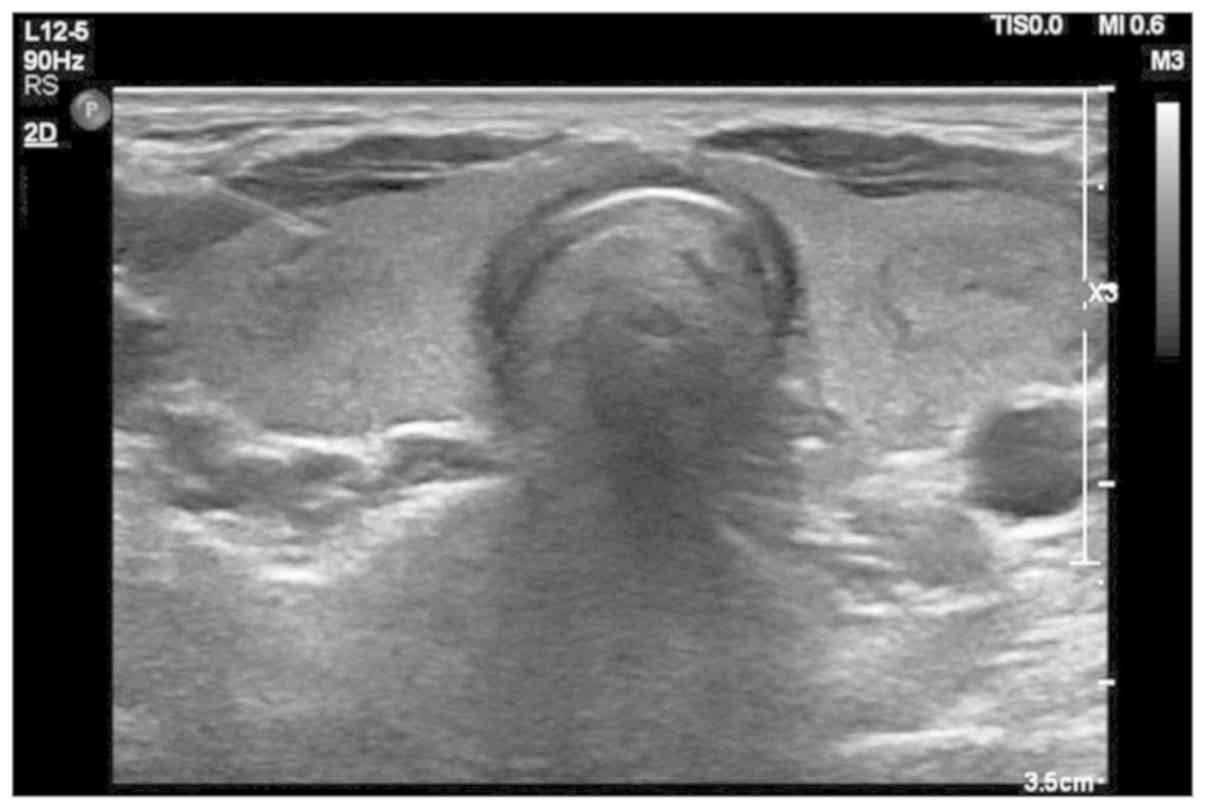

71 High Resolution Ultrasound thyroid showing thyroid nodule with increased vascularity 7 Imaging in Differentiated Thyroid Cancer 73 Fig. Preoperative ultrasonography US is the most sensitive method for detecting metastatic lymph nodes and is recommended as part of the standard preoperative workup.

The risk of cancer increased with the size of. 72 Strain Elastography of the thyroid nodule showing comparison between Normal lobe and the nodule Fig. The use of ultrasound for thyroid cancer has evolved dramatically over the last few decades.

74 High Resolution Ultrasound of thyroid showing hypoechoic lesion with illdefined. There is no blood test that can detect thyroid cancer. Colour flow patterns.